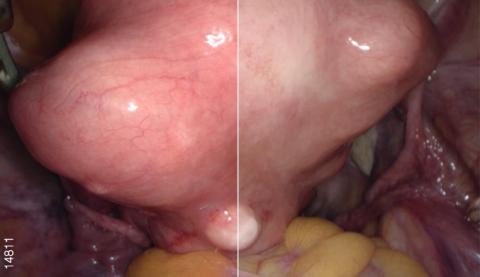

Первая система с изображением 4К Ultra HD

Видеоэндоскопическая система OLYMPUS VISERA 4K UHD обладает высококачественным изображением 4K и технологией узкоспектральной визуализации изображения NBI. Высокое разрешение позволяет визуализировать малейшие изменения в структуре тканей для ранней диагностики очагов воспаления и опухолей. Чем выше разрешение изображения, тем больше вероятность обнаружения очаговых изменений на ранней стадии. Процессор OTV-S400 позволяет получать изображения с разрешением 3840 х 2160 пикселей, что помогает увидеть значительно больше. Система поддерживает визуализацию в форматах 4K UHD (3840 × 2160) и Full 4K (4096 × 2160).

Количество получаемой информации в 4 раза больше, чем при работе на обычных системах для визуализации изображения Full HD. Увеличенный объем информации означает и увеличенное количество деталей, которые можно рассмотреть.Сверхвысокая четкость

Видеосистема обладает сверхвысокой четкостью изображения. Точная настройка каждого слоя формирования изображения и идеальное устройство каждой функции означают оптимизацию изображений для хирургического вмешательства. Сверхвысокая четкость также обеспечивает улучшенную видимость изображения, которая позволяет хирургам проводить более безопасные и точные вмешательства.

Расширенная цветовая гамма

Видеопроцессор OTV-S400 создает расширенную цветовую гамму за счет использования формата цвета 4K (BT2020). Это обеспечивает насыщенную цветопередачу и соответствующие цвета для каждой области. Благодаря этому происходит упрощение определения границ тканей (жира, нервов, сосудов и т. п.) и улучшенная визуализация кровеносных сосудов и пораженных участков.